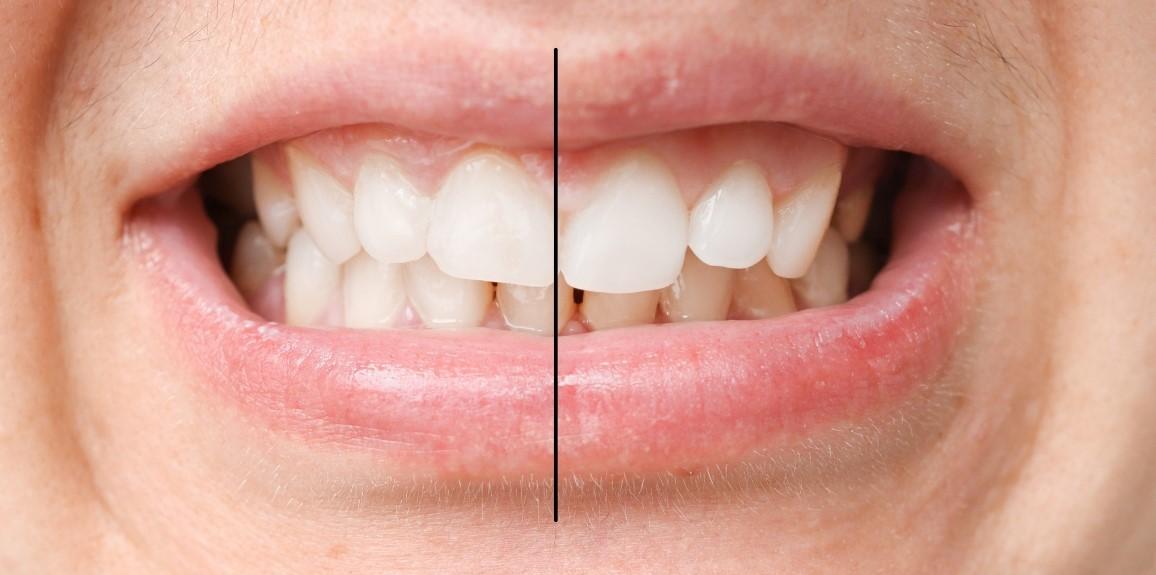

ずれている?正常?まずは歯並びチェック

まずは、ご自身の歯並びが正常なのかそれともずれているのか、セルフチェックから始めましょう。一般的に、以下の条件をすべて満たしているなら歯並びは正常であるといわれています。

【条件①】前歯の間の線が上下繋がっている

正常な歯並びの方は、上の歯と下の歯の中心が繋がり、一本の線になっています。もし繋がっていない場合、左右の噛み合わせが非対称となって上か下の歯が横にずれていることになります。